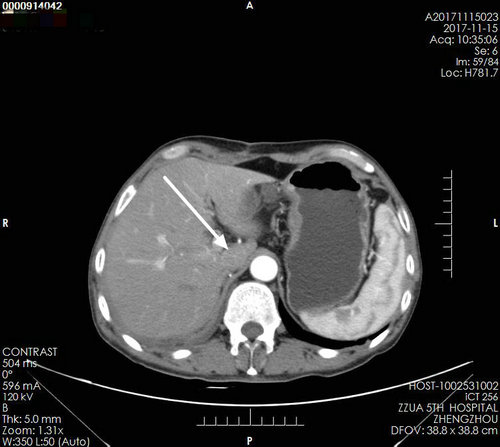

▲ 术后复查影像

术后复查:下腔静脉通畅,腔内CT值均匀,未见填充物,右肾区由肠管填充,未见肿瘤残留及复发。